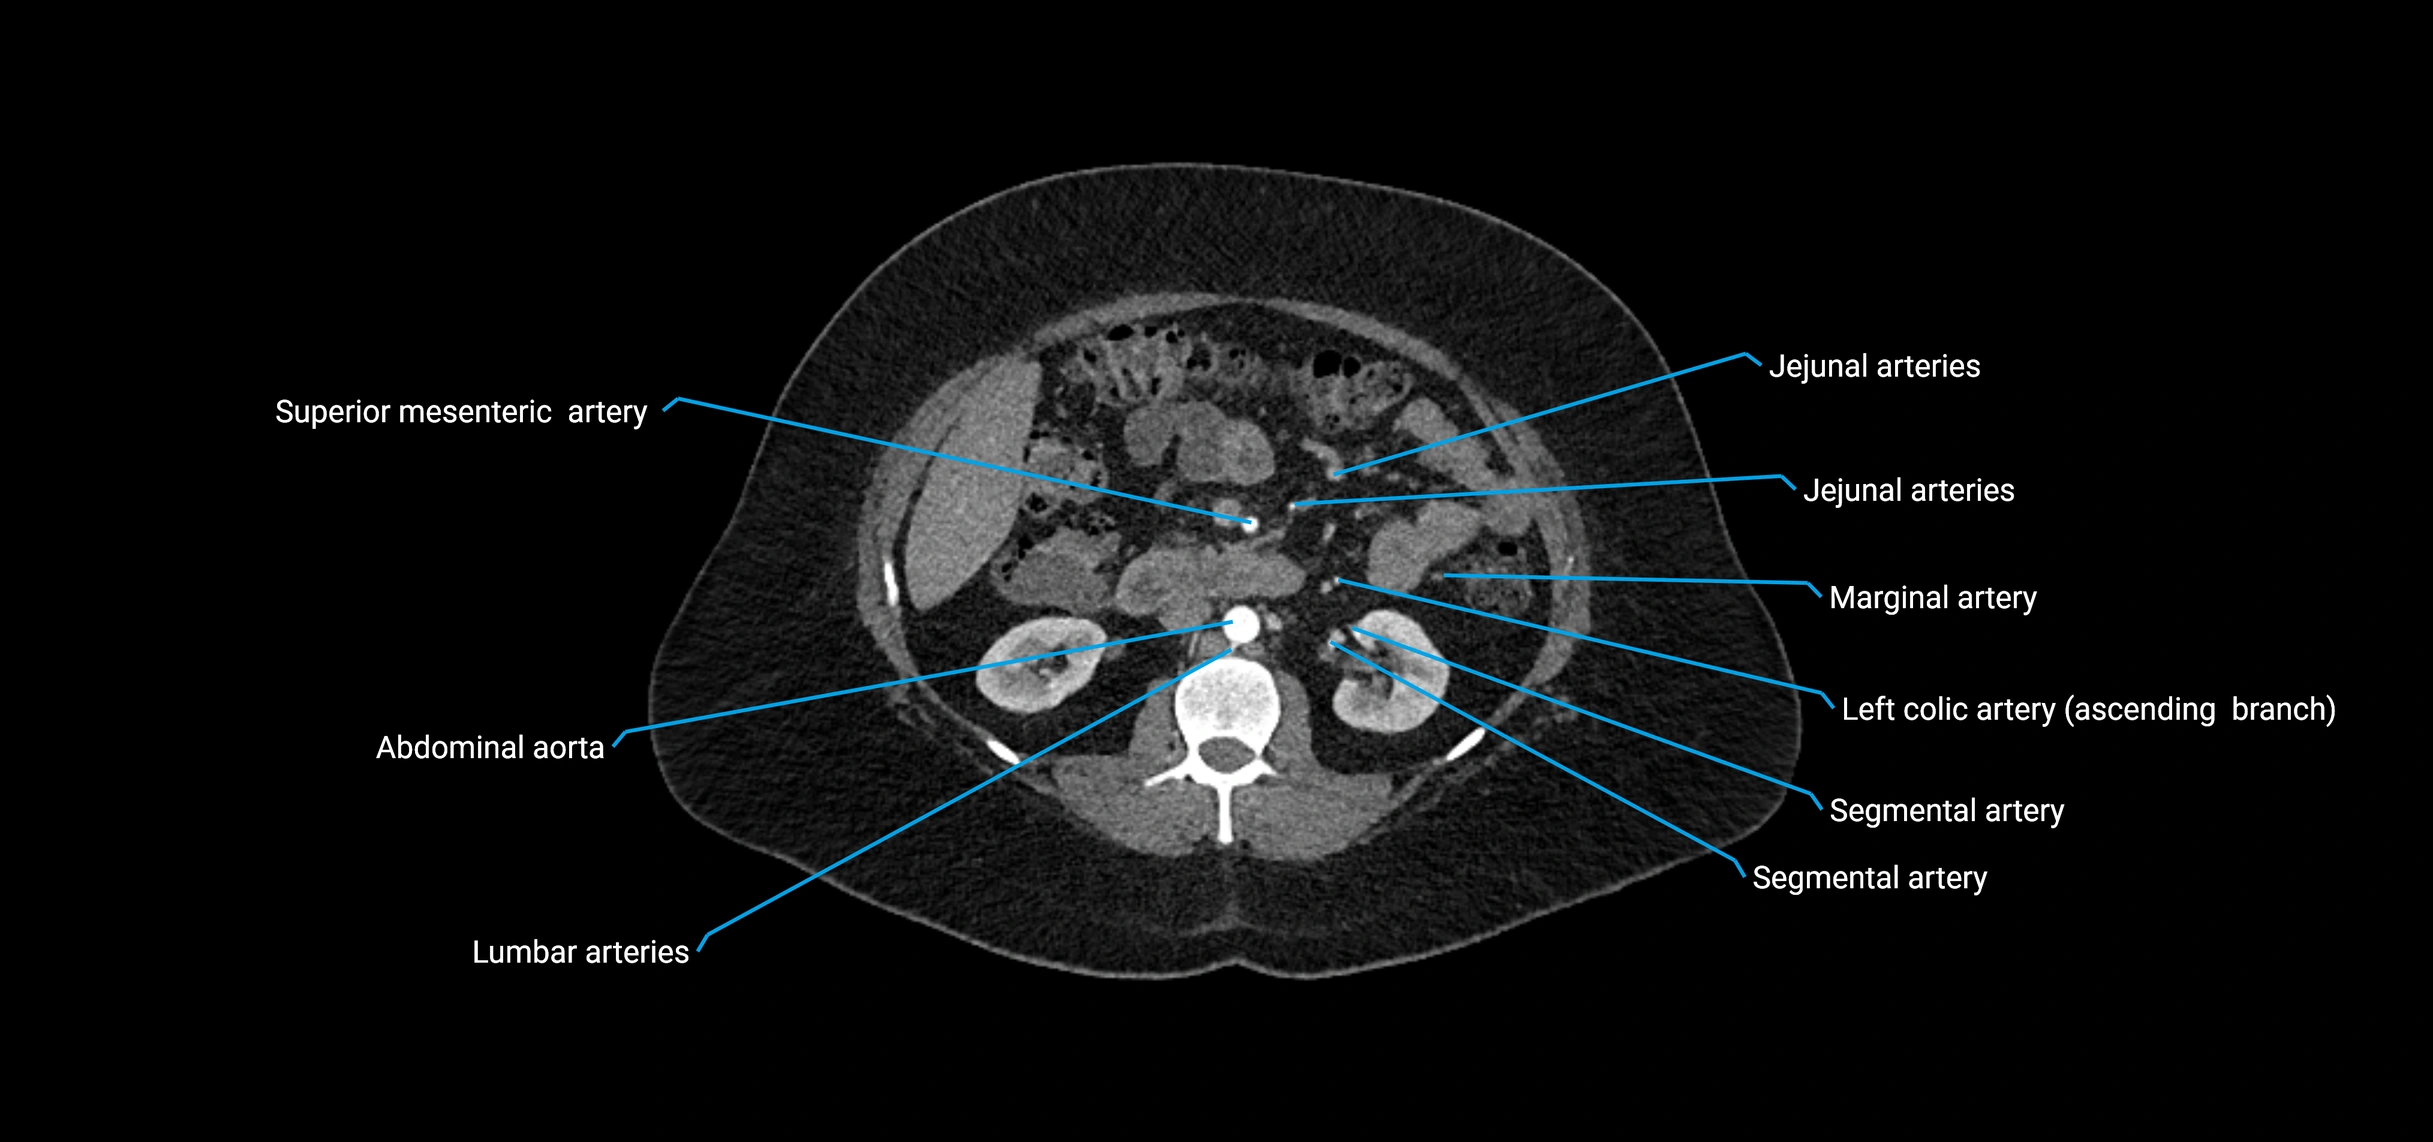

Contrast-enhanced CT (CTA):

• Gold standard for abdominal aortic imaging

• Provides excellent detail of lumen, wall, aneurysm, thrombus, and branch vessels

• Multiplanar and 3D reconstructions help in aneurysm measurement, stent graft planning, and dissection evaluation

• Detects acute rupture, traumatic injury, or occlusion with high sensitivity